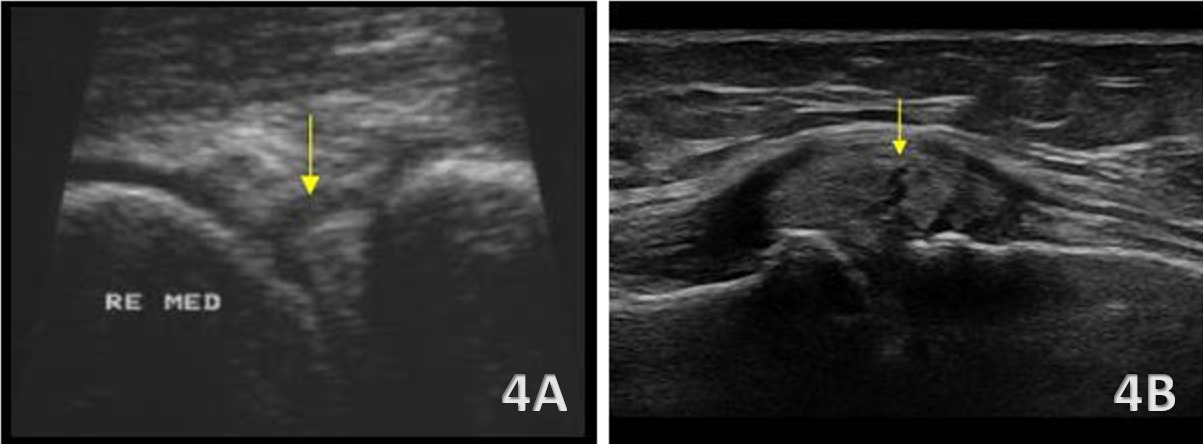

Medial Meniscus Tear and Cyst Formation

Figures 4A and 4B: Tears of the medial meniscus are often more readily visualized due to its superficial location and firm attachment to the joint capsule and MCL. Sonographic findings include loss of the normal triangular contour, focal hypoechoic or anechoic clefts within the meniscal body as seen above in Figure 4A, and extrusion beyond the medial tibial margin as seen above in Figure 4B. Associated findings such as joint line fluid, capsular thickening, or adjacent MCL involvement are common and may further support the diagnosis, particularly in degenerative or chronic presentations.